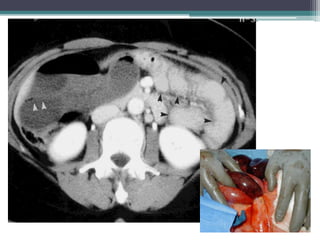

Tài liệu bàn về tắc ruột, bao gồm định nghĩa, phân loại và nguyên nhân của tình trạng này, với sự phân biệt giữa tắc cơ học và cơ năng. Các triệu chứng và chẩn đoán lâm sàng được trình bày, kèm theo phương pháp chẩn đoán cận lâm sàng như x-quang và siêu âm. Ngoài ra, tài liệu cũng đề cập đến các biến chứng và hậu quả của tắc ruột.